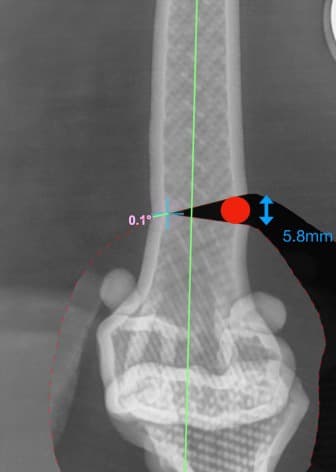

13수술 중 골절 상태 혹은 이식물 적용 후 상태 등 육안으로 명확히 확인하기 힘든 상태를 X-ray 확인하여 정확한 수술 결과를 만들어 내는 것이 가능